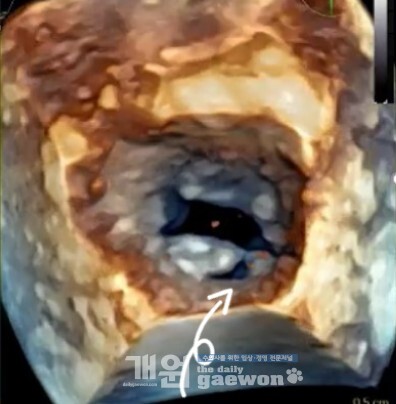

3D 에서도 마찬가지. 양쪽 판막이 닫힌 상태에서도 여전히 gap (빨간색 화살표가 가리키는 검정색 틈)이 확인된다.

너무 오래된 심장병이었고, 심장이 오랜시칸 크게 유지중이었고 (= 판막륜이 오랫동안 큰 상태였고), 판막사이의 길이를 더한 값이 판막륜보다 작거나 같았다.

판막의 퇴행성 변화는 적지만, 판막륜이 너무 크다. 판막 사이의 horizontal gap이

확인된다.